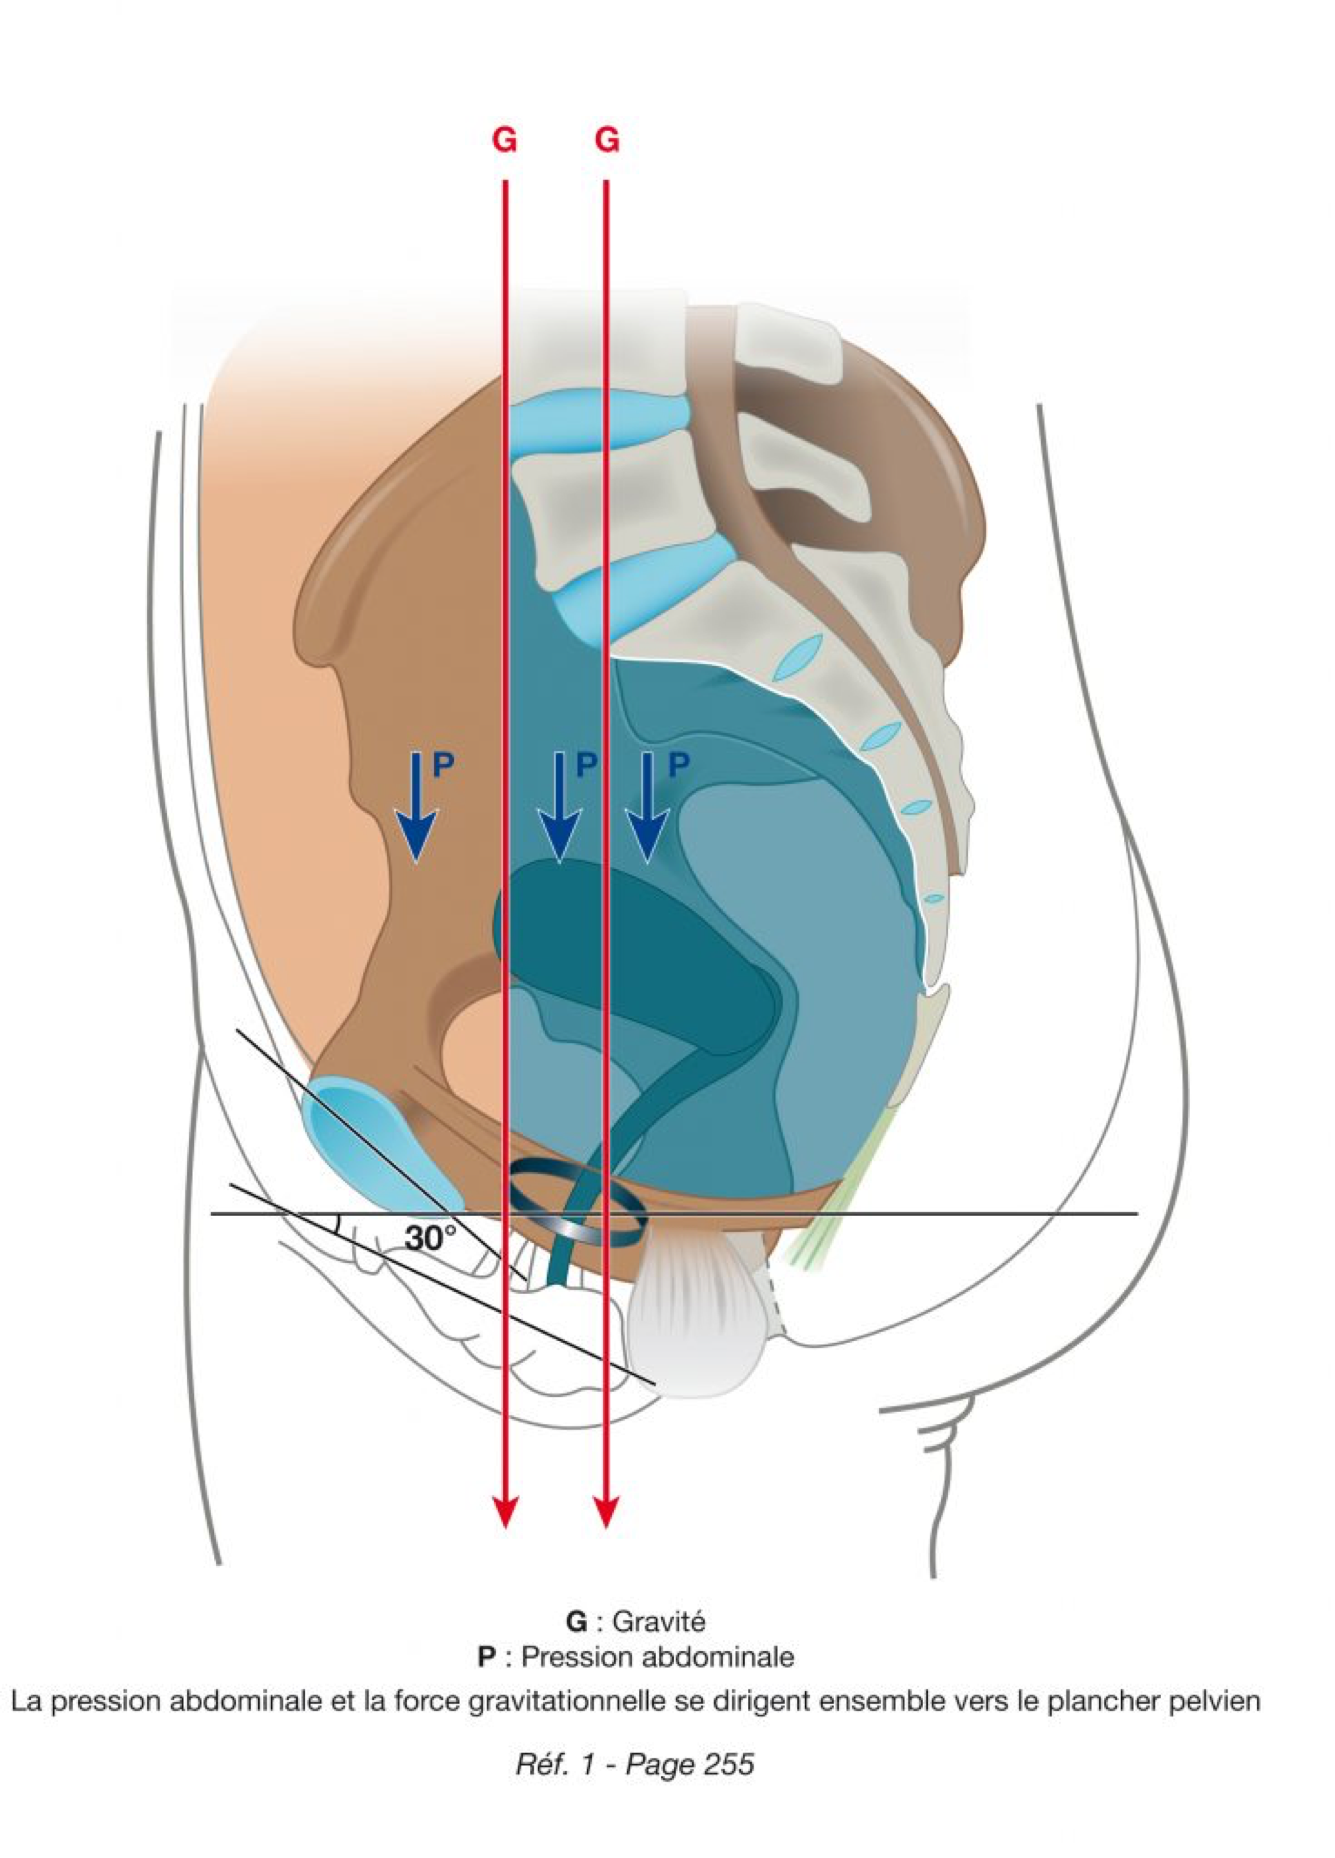

Nous avons appris que les pressions abdominales se dirigent vers le plancher pelvien, dans le sens de la gravité terrestre (le postulat gravitationnel).

L’humain(e) est un(e) Homo Erectus (Kamina – ref 1 – P253-257). Au cours de l’évolution la force gravitationnelle se dirige progressivement vers le bas, vers le plancher pelvien. Par excès simplificateur, on en vient à penser que la pression abdominale et la force gravitationnelle ne s’exercent plus que SUR le plancher pelvien. De nombreux paradoxes physiologiques ou pathologiques apparaissent alors.

Le postulat gravitationnel est décrit dans le « Traité d'anatomie de Kamina » (ref 1 P252-257). La pression abdominale et la pression gravitationnelle se dirigent, ensemble, vers le «plancher» pelvien, constitué essentiellement par le groupe des muscles releveurs.